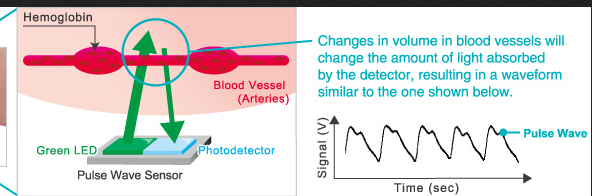

Why Is AB Blood Type So Rare? It’s All About The Red Blood Cells

Mar 25, 2016 – “Blood group A has only A antigens.” Similarly, blood group B has only B antigens, blood group AB has both, and blood group O has neither A nor B antigens on the surface of the red blood cells. These four groups are the most important because they indicate which blood type a patient can safely receive in a transfusion.

AB Positive Blood Type Facts

about Lord Byron arteries OUTPUT messages|

Thrombocytes

AB Positive Blood Type Facts (AB+). 1. Universal Plasma Donor and Universal Red Cell Recipient. The nature of antigens present in the serum determines the …

Blood type – Wikipedia

A blood type is a classification of blood based on the presence and absence of antibodies and …. Therefore, an individual with type AB blood can receive blood from any group (with AB being preferable), but cannot donate blood to any group …

Heme | definition of heme by Medical dictionary

Heme binds and carries oxygen in the red blood cells, releasing it to tissues. Also spelled haeme. See also hemoglobin, porphobilinogen, protoporphyrin.

Heme | definition of heme

Heme | definition of heme OUTPUT formats

Heme | definition of Theme …. SCheme